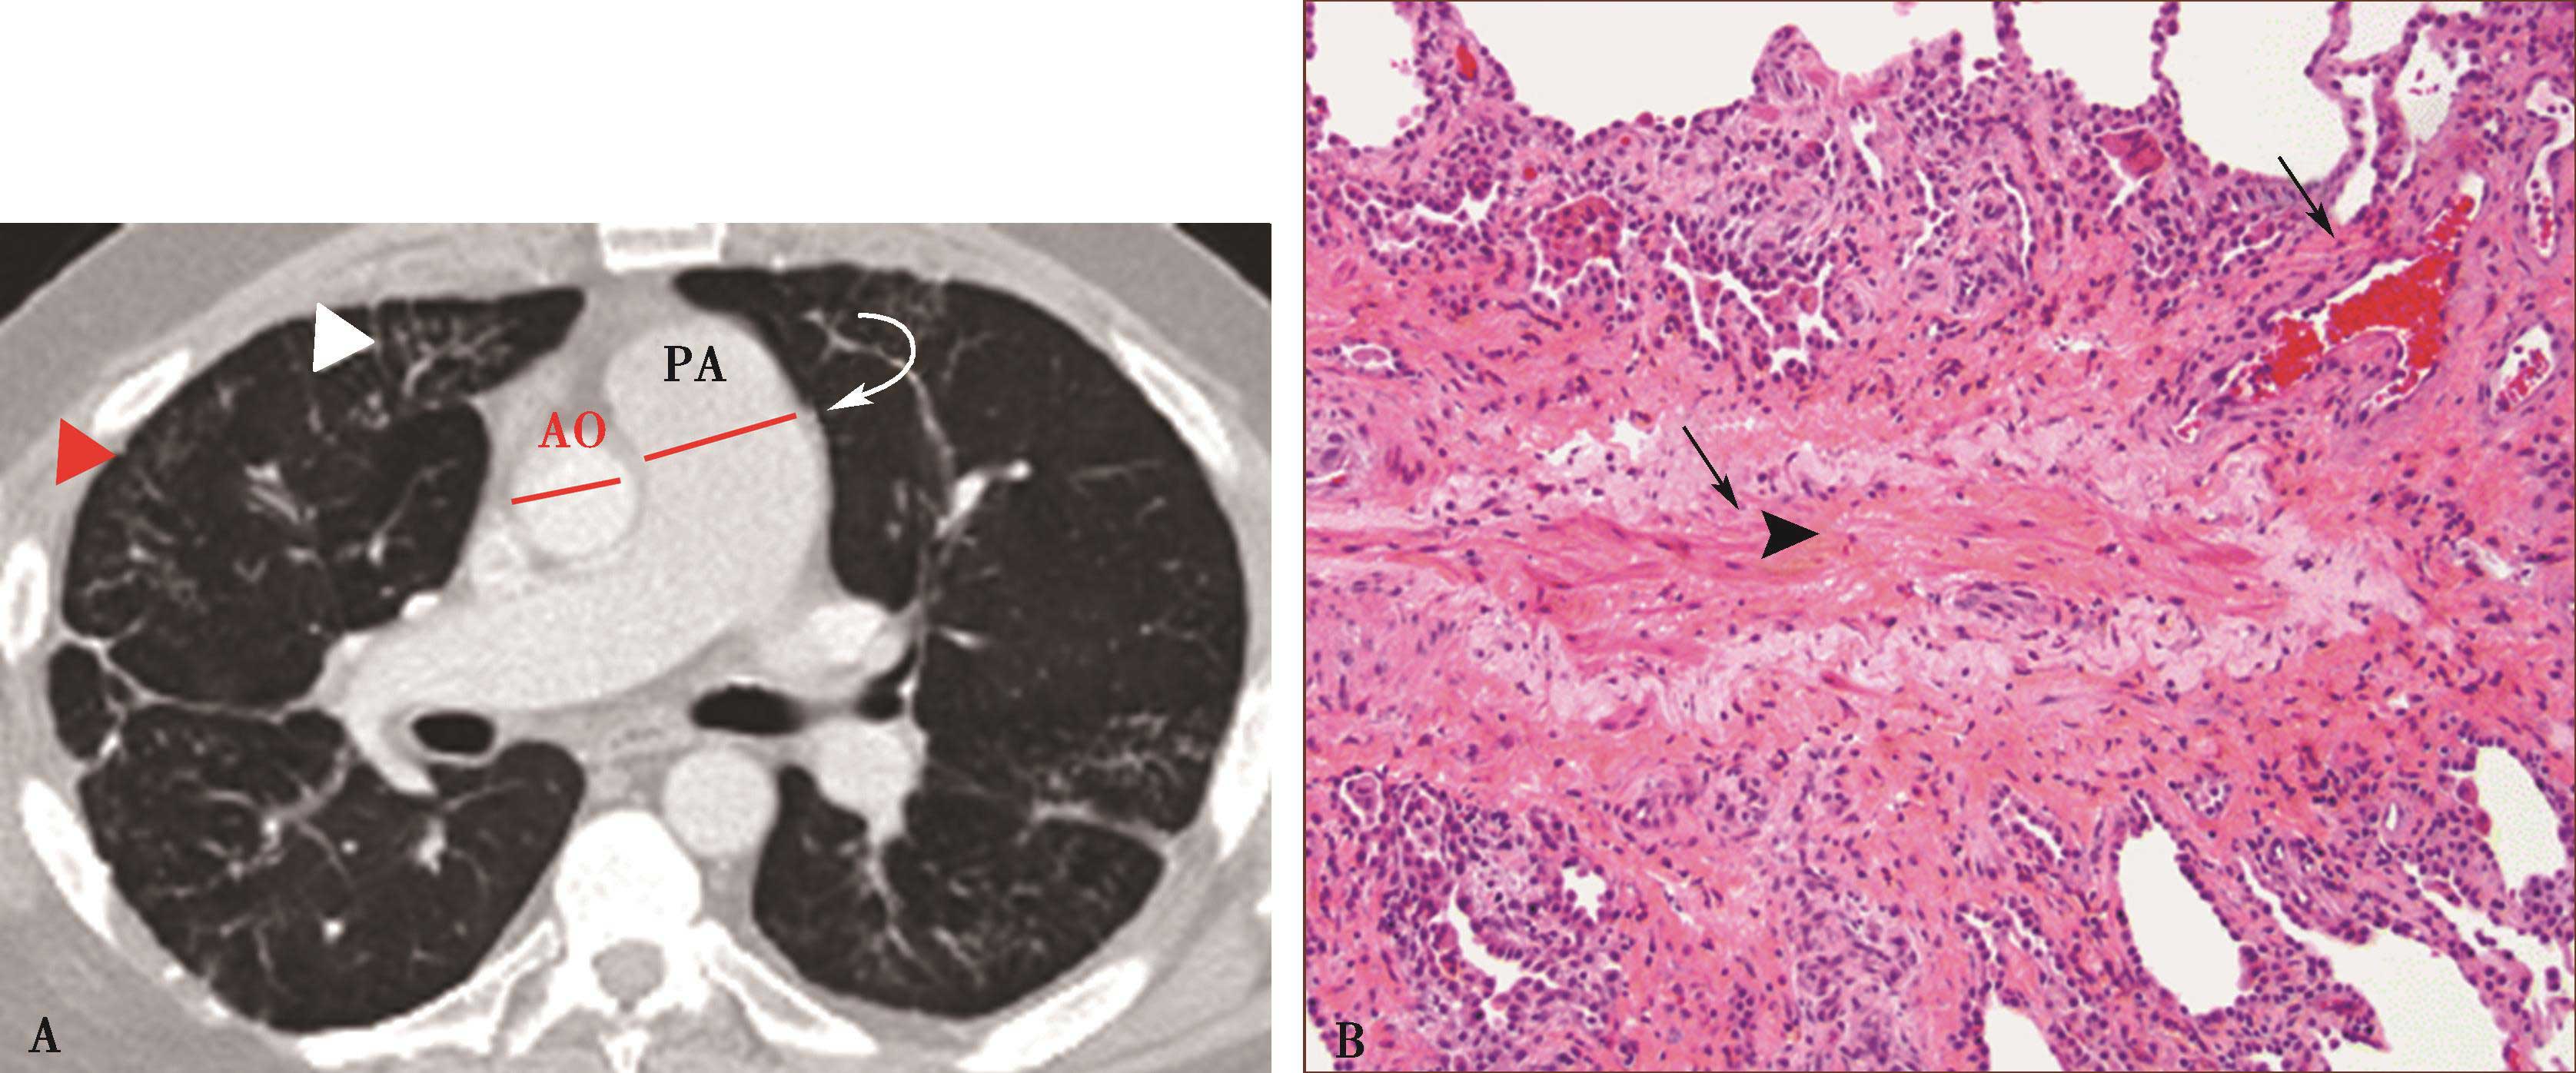

图8-5-6 坏死性肉芽肿性血管炎(韦格纳肉芽肿)

A.胸部X线片,两肺多发结节,不规则空洞形成(↑);B~D.横断图像,两上、下肺多发不规则结节肿块,大小不等,不规则空洞形成,壁薄厚不一,边缘不规则,液平形成;病理检查:E.肺小血管横断面,显示炎性细胞浸润累及部分血管;F.肺小血管纵切面,炎性细胞浸润,部分管壁破坏。CT诊断:韦格纳肉芽肿(病理证实为坏死性肉芽肿性血管炎)